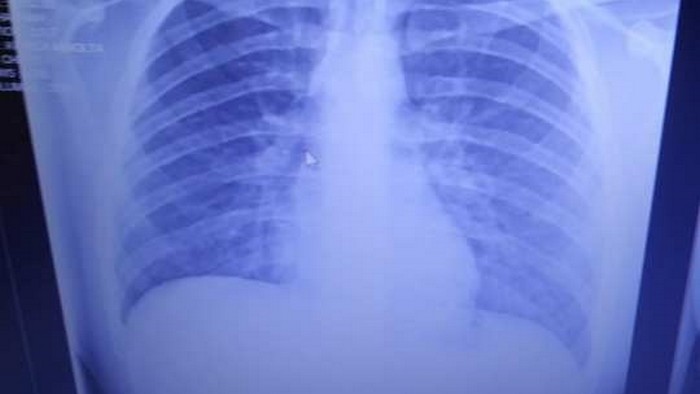

Житель города Эри, США, 19-летний Энтони Майо шокировал врачей видом своих легких после курения вейпа. Об этом сообщает Metro US.

Парень попал в больницу в начале сентября с приступом удушья и серьезным кашлем. Сначала специалисты решили, что у парня бронхит. Но 15 сентября Майо доставили в отделение неотложной помощи. Сообщается, что уровень кислорода в организме парня составлял 36%, при том, что уровень ниже 90% считается критическим.

Врачи обнаружили в легких парня застывшее масло для вейпа. Они сравнили его с застывающим бетоном. Врачи ищут способ вновь "растопить" масло и вывести его из легких.

Сообщается, что парень регулярно курил вейп на протяжении двух лет. Сейчас его легкие похожие на легкие 60-летнего человека, выкуривающего по две пачки сигарет в день.

Специалисты подчеркивают, что из легких Майо выходила жидкость кроваво-красного, коричневого и темно-зеленого цвета. При этом его легкие получили такой ущерб, что орган может уже не восстановиться.